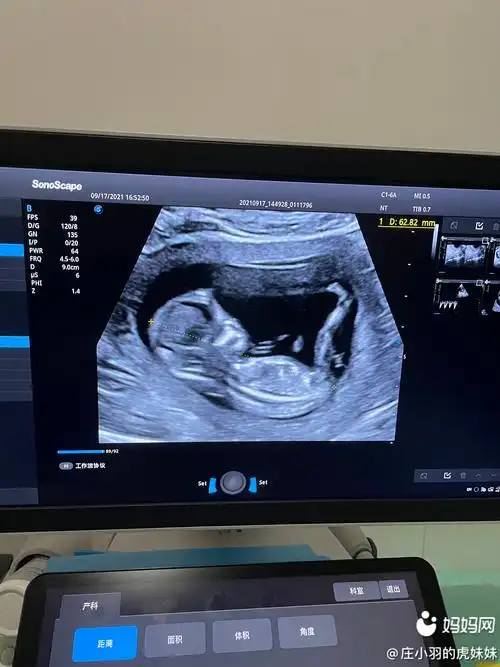

nt做了四次,不是侧睡就是趴着,还是过了,一切正正 | 妈妈网轻聊_千万